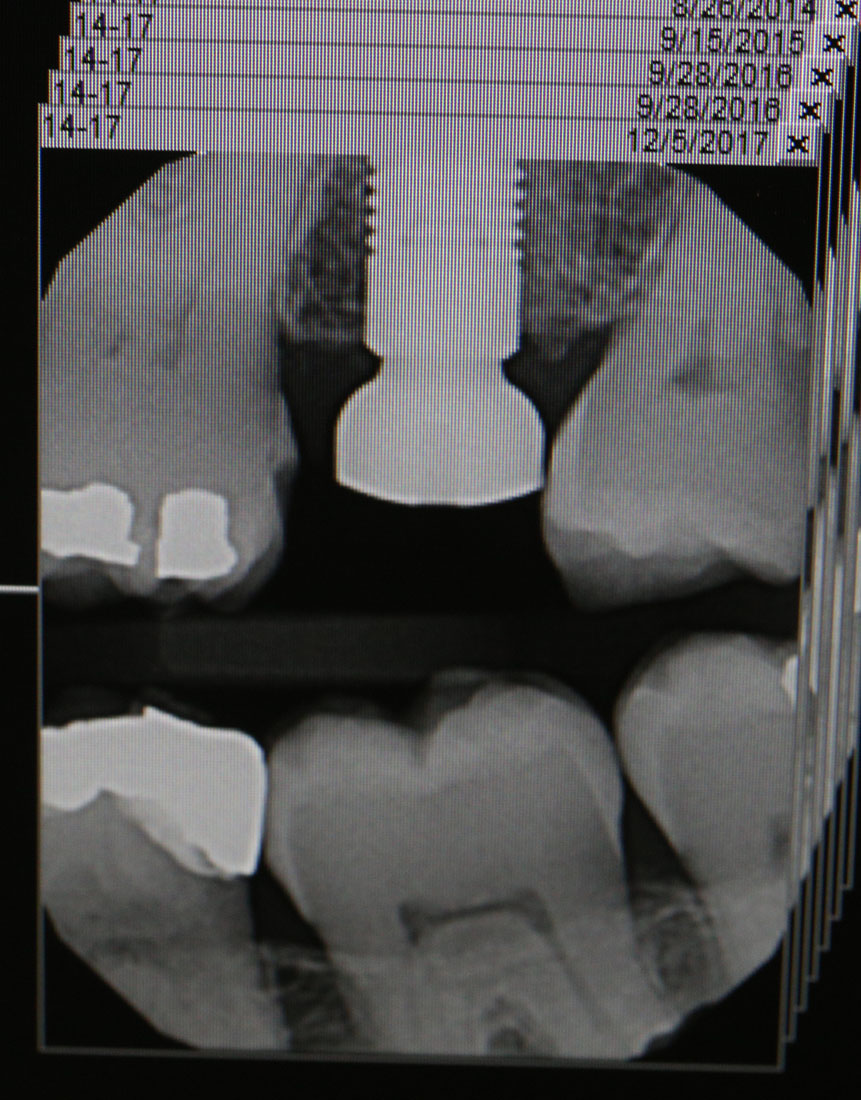

I got a new tooth implant a couple weeks ago. The exact need and timing is sort of lost in the blur of time, but I believe the cause was that I had a cavity under a crown (this more than 2 years ago!). Dr. Chang cleaned out the cavity, but there wasn't enough of a stump to fasten a new crown, so the root was extracted and bone graft installed (by oral surgeon). I vaguely recall that because there was a bleeding issue (since I'm on blood thinners), and had to go in for assistance to stop it. Eventually it took, and a few months later, the titanium threaded insert was installed - all was well. I sort of forgot about it, but a couple months ago, Dr. Chang reminded me we had it hanging over me, so after a session with a mouth full of modeling putty, a couple months later I had a new tooth! That is my always-smiling Dr. Chang at left, and at right is an x-ray of the titanium threaded insert and bolt that was in place for something over a year and a half!

After the snug check in the plaster cast above, he tried it in the real gap in my mouth. It went in, but interesting he couldn't get it back out! He didn't really panic, but had wanted to remove it to polish it up some, perhaps take a little off where it was binding. Not wanting to damage any neighboring teeth or the implant, he eventually left it in place and placed the bolt in place - yes, using an official torque wrench at left! It really is a little Allen head hex bolt! After proper torque was applied, he filled the drive hole in the bolt with a little UV-curing cement, scraped it off level and it was done! He took one more x-ray of the finished product for the historical record, shown at right... Eventually the gaps will likely distribute more evenly, but I still can't get floss down both sides of the new one. I have an unrelated cleaning scheduled Thursday, so they will likely take another look at it then... For now, all paid for and all the ivories are "in the pink"!